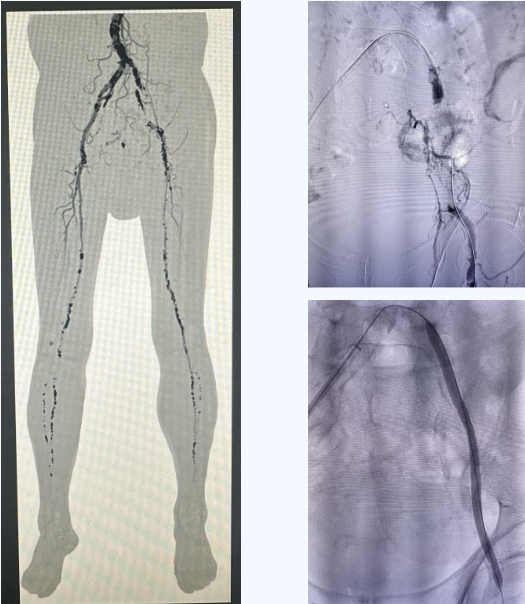

脑外科收治患者并完善相关检查发现:踝肱指数0.5,左下肢皮温低于右下肢,左侧足背、胫后、腘动脉搏动不明显。脑外科田德洲主任立即邀请北京大学第三医院韩金涛教授、刘启佳教授进行远程会诊,专家团队仔细研究患者病情,双下肢动脉闭塞,左下肢症状明显,经与患者及家属沟通征得同意,决定在局部麻醉下施行双下肢动脉造影+左髂动脉闭塞开通、球囊扩张成形术+支架置入术。

在北京大学第三医院韩金涛教授、刘启佳教授及我院田德洲主任的指导下,由董永军副主任、田垒医师与介入导管室医务人员密切配合,成功为患者实施左侧髂动脉闭塞开通成型术。术后恢复良好,患者感觉到左下肢明显温热,皮温明显升高。在护理团队的悉心护理下,术后第二天便可下床活动。